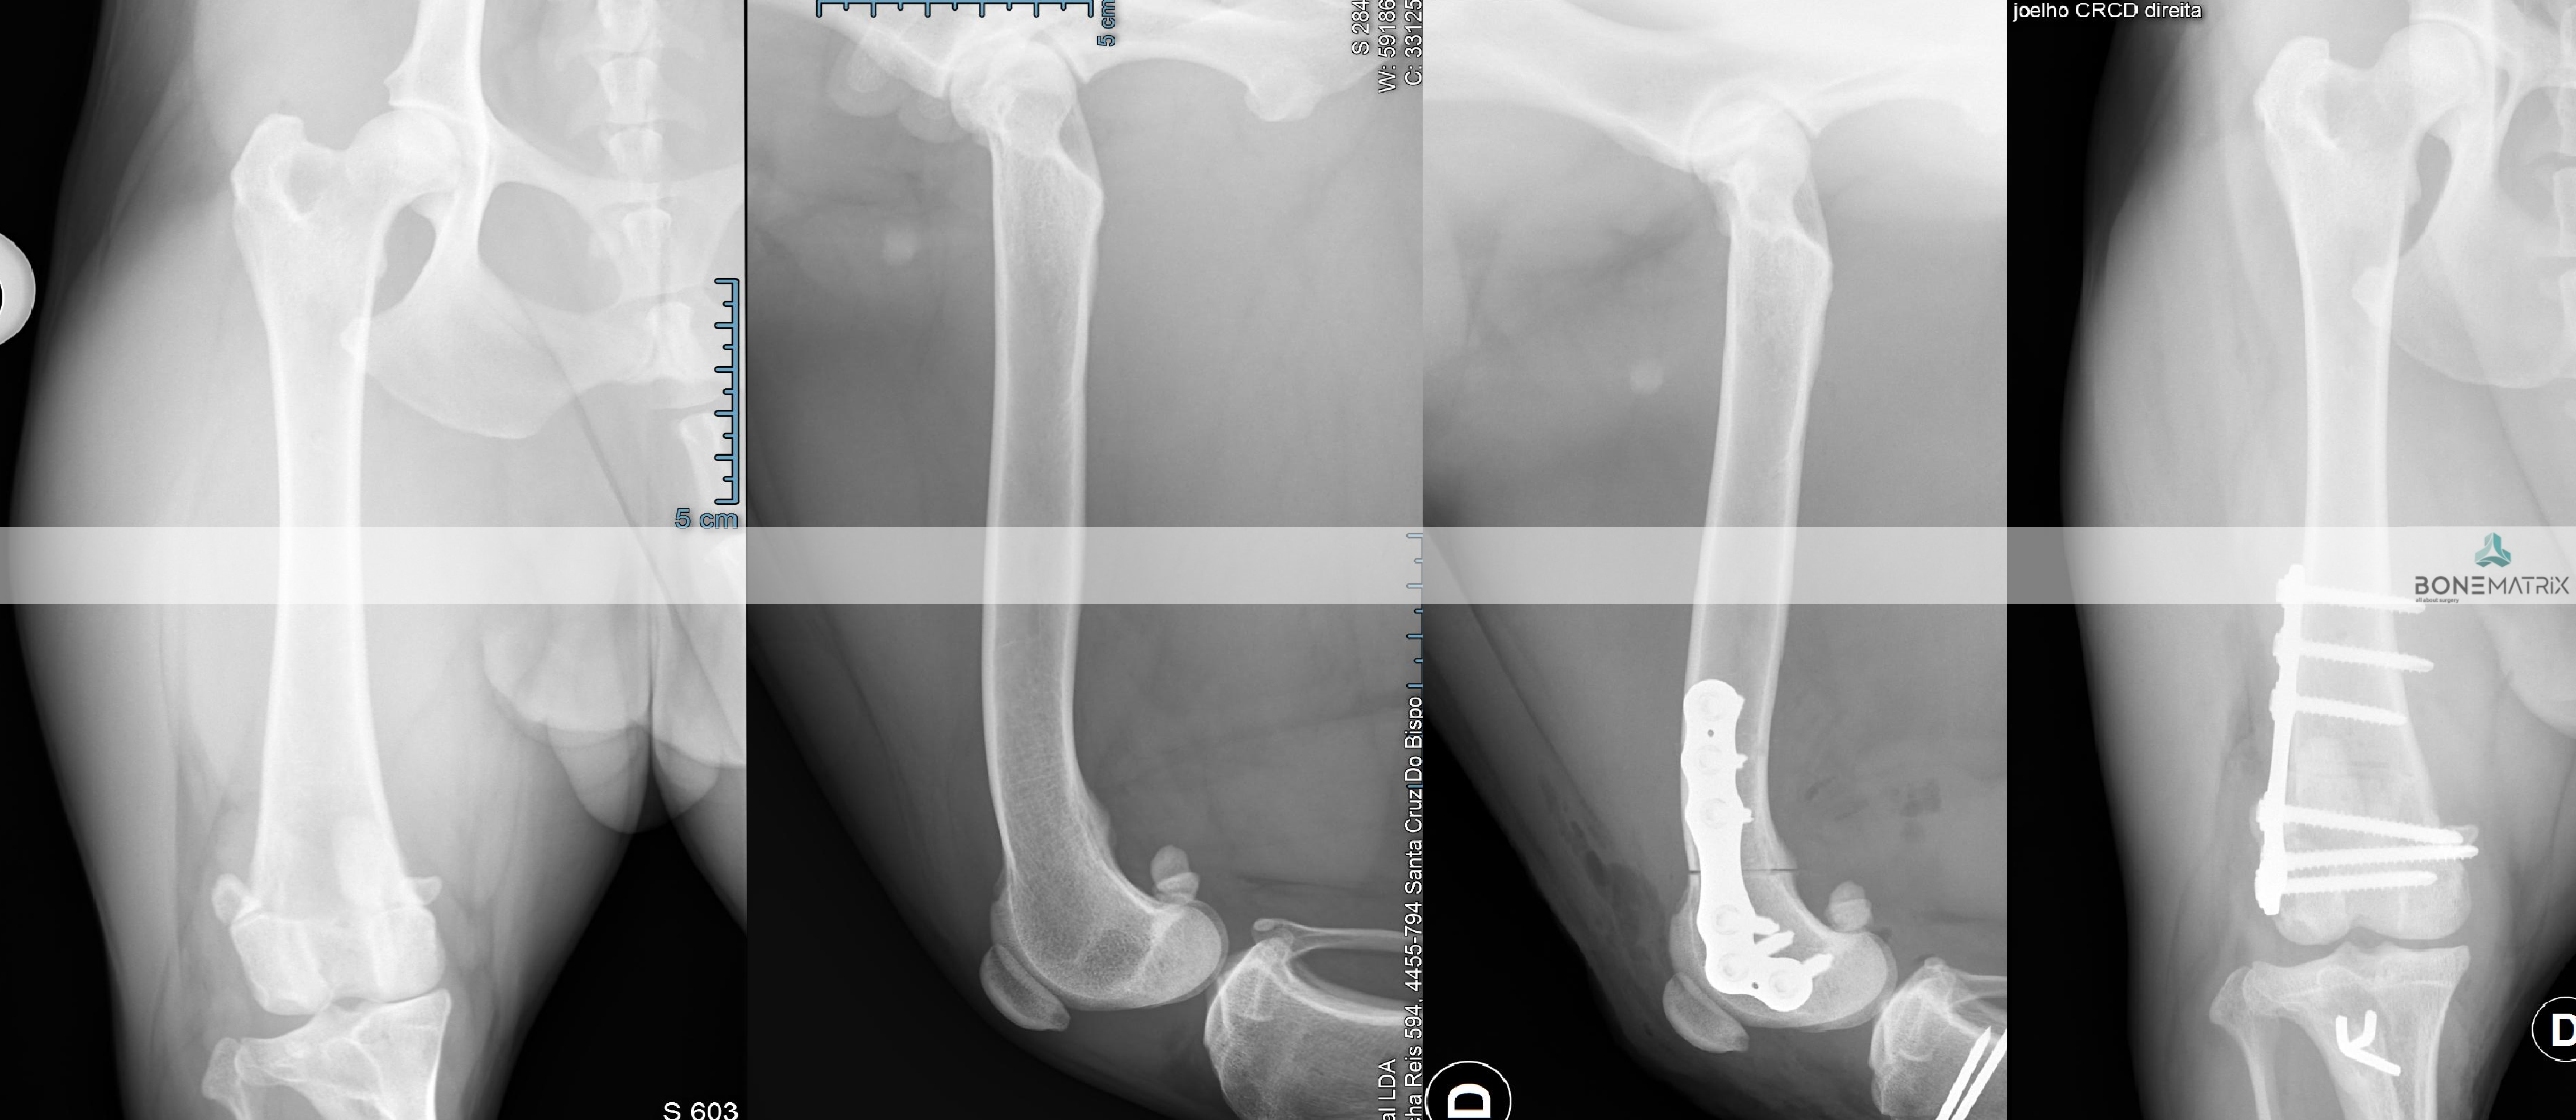

Esta técnica é maioritariamente aplicada em patologia de displasia de cotovelo.

A displasia do cotovelo apresenta várias formas, sendo que todas as apresentações têm em comum a existência de um crescimento assíncrono dos ossos constituintes da articulação.

Este crescimento assíncrono faz com que a ulna, o rádio ou o úmero não estejam perfeitamente posicionados dentro do espaço articular (incongruência articular). Esta incongruência resulta no sobrecarregamento de determinadas zonas dentro do cotovelo. O sobrecarregamento destas zonas provocam o desenvolvimento de lesões na cartilagem.

As lesões cartilagíneas, por si só assim como também por conduzirem ao desenvolvimento de quadros de osteoartrite, podem levar a processos de dor e desconforto bastante debilitantes para o animal.

Inicialmente deve ser realizado um despiste de displasia de cotovelo com recurso a um estudo radiográfico específico para que o paciente seja avaliado e seja definido como um bom candidato à aplicação desta técnica.

O que é a PLUS?

A PLUS (Petazzoni longitudinal ulnar slidding) é uma cirurgia realizada com o intuito de recuperação de congruência a nível articular, no cotovelo.

Esta cirurgia consiste na realização de um corte com características especificas na ulna que permite a sua movimentação deste osso e reajuste da sua posição dentro da articulação do cotovelo.

DPO (double pelvic osteotomy) é um procedimento preventivo realizado em pacientes onde o despiste de displasia de anca prevê o desenvolvimento desta doença.

Inicialmente deve ser realizado um despiste de displasia de anca com recurso a um estudo radiográfico especifico para que o paciente seja avaliado e seja definido como um bom candidato à aplicação desta técnica.

A DPO consiste na realização de dois cortes ao nível da pélvis que permitem a rotação do fragmento criado. Este fragmento inclui a porção articular da pélvis, na articulação coxofemoral (o acetábulo).

Ao rodar este fragmento conseguimos uma maior cobertura da cabeça femoral pelo acetábulo, impedindo o movimento de saída da cabeça femoral de dentro do acetábulo. Ao impedir este movimento (laxitude articular) impedimos o desenvolvimento de lesões de osteoartrite provocada por ele, e desta forma impedimos o desenvolvimento da doença de displasia de anca.

Após rotação do fragmento, este é estabilizado na posição pretendida com recurso a placas bloqueadas especializadas para a realização desta cirurgia, garantindo assim a cicatrização do osso no ângulo previamente definido.